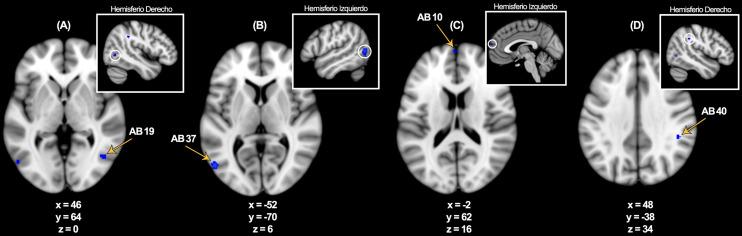

A meta-analysis was conducted using peer-reviewed, event-related fMRI studies. The Activation Likelihood Estimation (ALE) method was applied via GingerALE software to compare brain activations associated with the encoding of affective visual stimuli presented as either words or photographs. Three contrasts were assessed: pictures > neutral + control, words > neutral + control, and overlap between both.

Picture stimuli elicited bilateral activation in the medial parahippocampus, while word stimuli produced left-lateralized activation in the lateral parahippocampus. The overlap analysis identified a shared region in the parahippocampal amygdala. All three contrasts revealed significant activations in key medial temporal lobe (MTL) regions involved in emotional memory, including the hippocampus and amygdala.

使用同行评审的事件相关fMRI研究进行荟萃分析。通过GingerALE软件应用激活可能性估计(ALE)方法,比较与以单词或照片形式呈现的情感视觉刺激编码相关的脑激活。评估了三个对比:图片>中性+对照、单词>中性+对照以及两者之间的重叠。

图片刺激在内侧海马旁回引发双侧激活,而单词刺激在外侧海马旁回产生左侧化激活。重叠分析确定了海马旁杏仁核中的一个共享区域。所有三个对比在参与情绪记忆的关键内侧颞叶(MTL)区域均显示出显著激活,包括海马体和杏仁核。